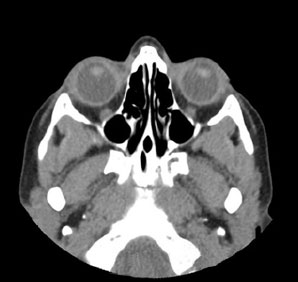

Tomografía computarizada Órbitas

< Volver a "Tomografía Computarizada (TC) con Inteligencia artificial"Está indicado para el estudio de los globos oculares o de los huesos de las órbitas (traumatismos).